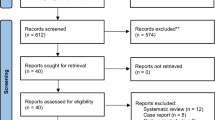

The novel robot-assisted (RA) technique has been utilized increasingly to improve the accuracy of cervical pedicle screw placement. Although the clinical application of the RA technique has been investigated in several case series and comparative studies, the superiority and safety of RA over conventional freehand (FH) methods remain controversial. Meanwhile, the intra-pedicular accuracy of the two methods has not been compared for patients with cervical traumatic conditions. This study aimed to compare the rate and risk factors of intra-pedicular accuracy of RA versus the conventional FH approach for posterior pedicle screw placement in cervical traumatic diseases. A total of 52 patients with cervical traumatic diseases who received cervical screw placement using RA (26 patients) and FH (26 patients) techniques were retrospectively included. The primary outcome was the intra-pedicular accuracy of cervical pedicle screw placement according to the Gertzbin–Robbins scale. Secondary outcome parameters included surgical time, intraoperative blood loss, postoperative drainage, postoperative hospital stay, and complications. Moreover, the risk factors that possibly affected intra-pedicular accuracy were assessed using univariate analyses. Out of 52 screws inserted using the RA method, 43 screws (82.7%) were classified as grade A, with the remaining 7 (13.5%) and 2 (3.8%) screws classified as grades B and C. In the FH cohort, 60.8% of the 79 screws were graded A, with the remaining screws graded B (21, 26.6%), C (8, 10.1%), and D (2, 2.5%). The RA technique showed a significantly higher rate of optimal intra-pedicular accuracy than the FH method (P = 0.008), but there was no significant difference between the two groups in terms of clinically acceptable accuracy (P = 0.161). Besides, the RA technique showed remarkably longer surgery time, less postoperative drainage, shorter postoperative hospital stay, and equivalent intraoperative blood loss and complications than the FH technique. Furthermore, the univariate analyses showed that severe obliquity of the lateral atlantoaxial joint in the coronal plane (P = 0.003) and shorter width of the lateral mass at the inferior margin of the posterior arch (P = 0.014) were risk factors related to the inaccuracy of C1 screw placement. The diagnosis of HRVA (P < 0.001), severe obliquity of the lateral atlantoaxial joint in the coronal plane (P < 0.001), short pedicle width (P < 0.001), and short pedicle height (P < 0.001) were risk factors related to the inaccuracy of C2 screw placement. RA cervical pedicle screw placement was associated with a higher rate of optimal intra-pedicular accuracy to the FH technique for patients with cervical traumatic conditions. The severe obliquity of the lateral atlantoaxial joint in the coronal plane independently contributed to high rates of the inaccuracy of C1 and C2 screw placements. RA pedicle screw placement is safe and useful for cervical traumatic surgery.